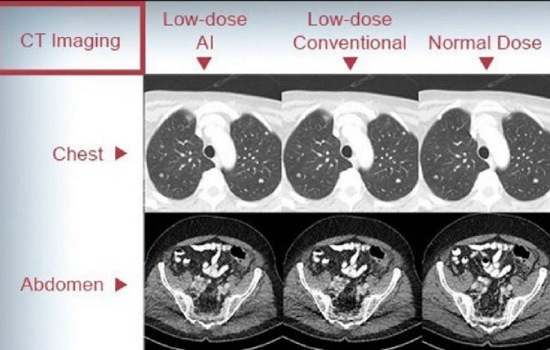

ในส่วนของมะเร็งปอดในกลุ่มผู้ไม่สูบบุหรี่นั้น จากข้อมูลที่ควรรู้ประมาณ 40-60 % ของมะเร็งปอดเกิดในผู้ที่ไม่เคยสูบบุหรี่ซึ่งมักเกิดจากการได้รับควันบุหรี่มือสอง, การสัมผัสก๊าซเรดอน, การสัมผัสสารพิษจากงานอาชีพ (เช่น แร่ใยหิน ควันดีเซล), มลพิษทางอากาศ หรือ ครัวเรือน, ประวัติครอบครัวเป็นมะเร็งปอด, การกลายพันธุ์ทางพันธุกรรม (เช่น EGFR, ALK) โดยมะเร็งปอดในผู้ไม่สูบบุหรี่มักเป็นชนิด อะดีโนคาร์ซิโนมา (Adenocarcinoma) ซึ่งมากกว่า 60-70% มักถูกวินิจฉัยในระยะที่ลุกลามแล้ว เพราะไม่มีการตรวจคัดกรองที่เหมาะสมโดยปัจจุบันยังไม่มีแนวทางการตรวจคัดกรองสำหรับผู้ไม่สูบบุหรี่ระดับชาติหรือสากล ที่ แนะนำให้ตรวจ LDCT เป็นการตรวจเอกซเรย์คอมพิวเตอร์บริเวณทรวงอกด้วยปริมาณรังสีที่ต่ำมาก ใช้เพื่อคัดกรองมะเร็งปอดในระยะเริ่มต้นในผู้ที่ไม่เคยสูบบุหรี่ทั่วไป โดยผลจากการตรวจ LDCT พบว่า 1. อัตราความเสี่ยงต่อประโยชน์ยังไม่ชัดเจน (ตรวจพบผลลวงบ่อย, ได้รับรังสี) และ 2.ยังไม่มีหลักฐานชัดเจนว่าช่วยให้รอดชีวิตเพิ่มขึ้นในกลุ่มความเสี่ยงต่ำ

ส่วนข้อควรระวังและประเมินก่อนตรวจ LDCT นั้น แม้จะช่วยลดอัตราการเสียชีวิตจากมะเร็งปอดในกลุ่มเสี่ยงสูง แต่ก็มีข้อควรพิจารณา เช่น 1. ผลบวกลวง (False Positive) โดยอาจพบก้อนที่ไม่ใช่มะเร็ง ทำให้ต้องตรวจเพิ่มเติมหรือผ่าตัดโดยไม่จำเป็น 2.การได้รับรังสีซ้ำซ้อนและ 3.ความวิตกกังวลจากผลตรวจ โดยมีบางรายอาจมีข้อยกเว้นหรือกรณีพิเศษ อาจมีประโยชน์ต่อการคัดกรองความเสี่ยง ได้แก่ 1.ประวัติครอบครัวที่ชัดเจนว่าเคยเป็นมะเร็งปอด 2.การสัมผัสสารพิษจากสิ่งแวดล้อมหรือจากอาชีพอย่างมีนัยสำคัญและ 3.พันธุกรรมที่เสี่ยงต่อการเป็นมะเร็ง กรณีเหล่านี้ควรพูดคุยกับแพทย์ และพิจารณาอย่างรอบคอบร่วมกัน โดยมากจะอยู่ในบริบทของการวิจัยหรือติดตามเฝ้าระวังกลุ่มเสี่ยงสูง โดยปัจจุบันการใช้ฟิล์มเอกซเรย์ในการตรวจคัดกรองมะเร็งปอดหรือการเจาะเลือด ยังไม่ใช่วิธีมาตรฐานที่มีความแม่นยำอีกต่อไป ฉะนั้นใครที่มีความเสี่ยง อย่าลืมไปคัดกรองมะเร็งปอดโดยการทำ LDCT กันนะครับ